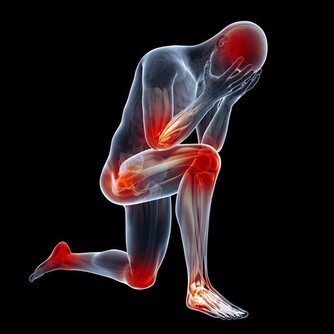

頸椎病、腰椎間盤突出、偏頭痛、肩周炎……生活中,人體許多部位都會遭到慢性疼痛的侵襲。

任何事情在發生之前,都會有一些徵兆,人體也一樣。

一些簡單的疼痛症狀,可能是身體給你發出的求救信號。

如果忽視它們,嚴重時甚至會致命。下面總結出7種可能要命的疼痛,遇到這些情況最好及時就醫。